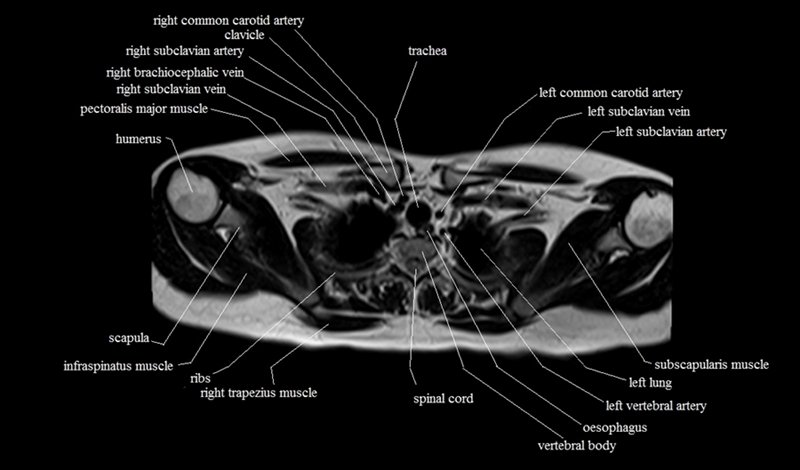

MRI Axial Cross Sectional Anatomy of Chest

This MRI chest (thorax) axial cross sectional anatomy tool is absolutely free to use. Use the mouse scroll wheel to move the images up and down, or alternatively, use the tiny arrows (→) on both sides of the image to navigate through the images. For a more detailed view, double-click the image to view it in full screen, and use the menu in the top right-hand corner to view individual slides or play them in a loop.